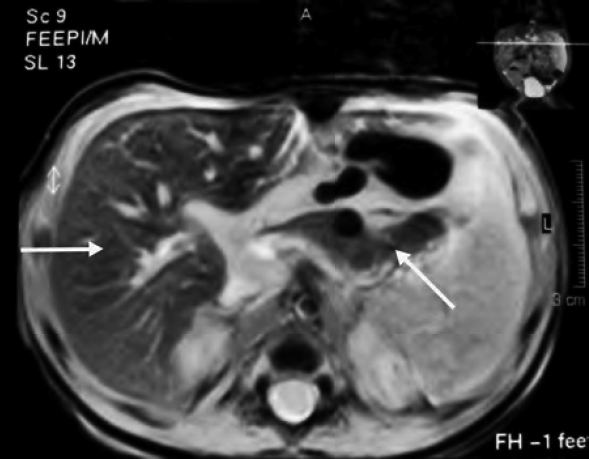

Una volta avanzato il sospetto, ed escluse le altre cause di insufficienza epatica in epoca neonatale, la diagnosi di certezza si ottiene documentando l�accumulo di ferro nei tessuti extraepatici10. Le indagini proposte a questo proposito sono la biopsia delle ghiandole salivari17,18 (Figura 1), che di per s� � un'indagine aspecifica, ma che assume un significato diagnostico importante inserita nel contesto clinico e laboratoristico4, e la risonanza magnetica (RM)8,19. Nel neonato con EN i depositi di ferro interessano tipicamente cuore, pancreas esocrino, tiroide e ghiandole sottomucose, che risultano quindi ipointensi nelle sequenze RM pesate in T2, risparmiando i tessuti del sistema reticolo endoteliale2,3: milza e linfonodi (Figura 2). Anche la siderosi epatica � evidente all�RM ma si tratta di un reperto non esclusivo di EN che in alcuni casi pu� addirittura mancare19,20.

Figura 2. Siderosi epatica e pancreatica (frecce): l�intensit� del segnale � marcatamente ridotta alle sequenze RMN pesate in T2. La milza � risparmiata. Da voce bibliografica 31.